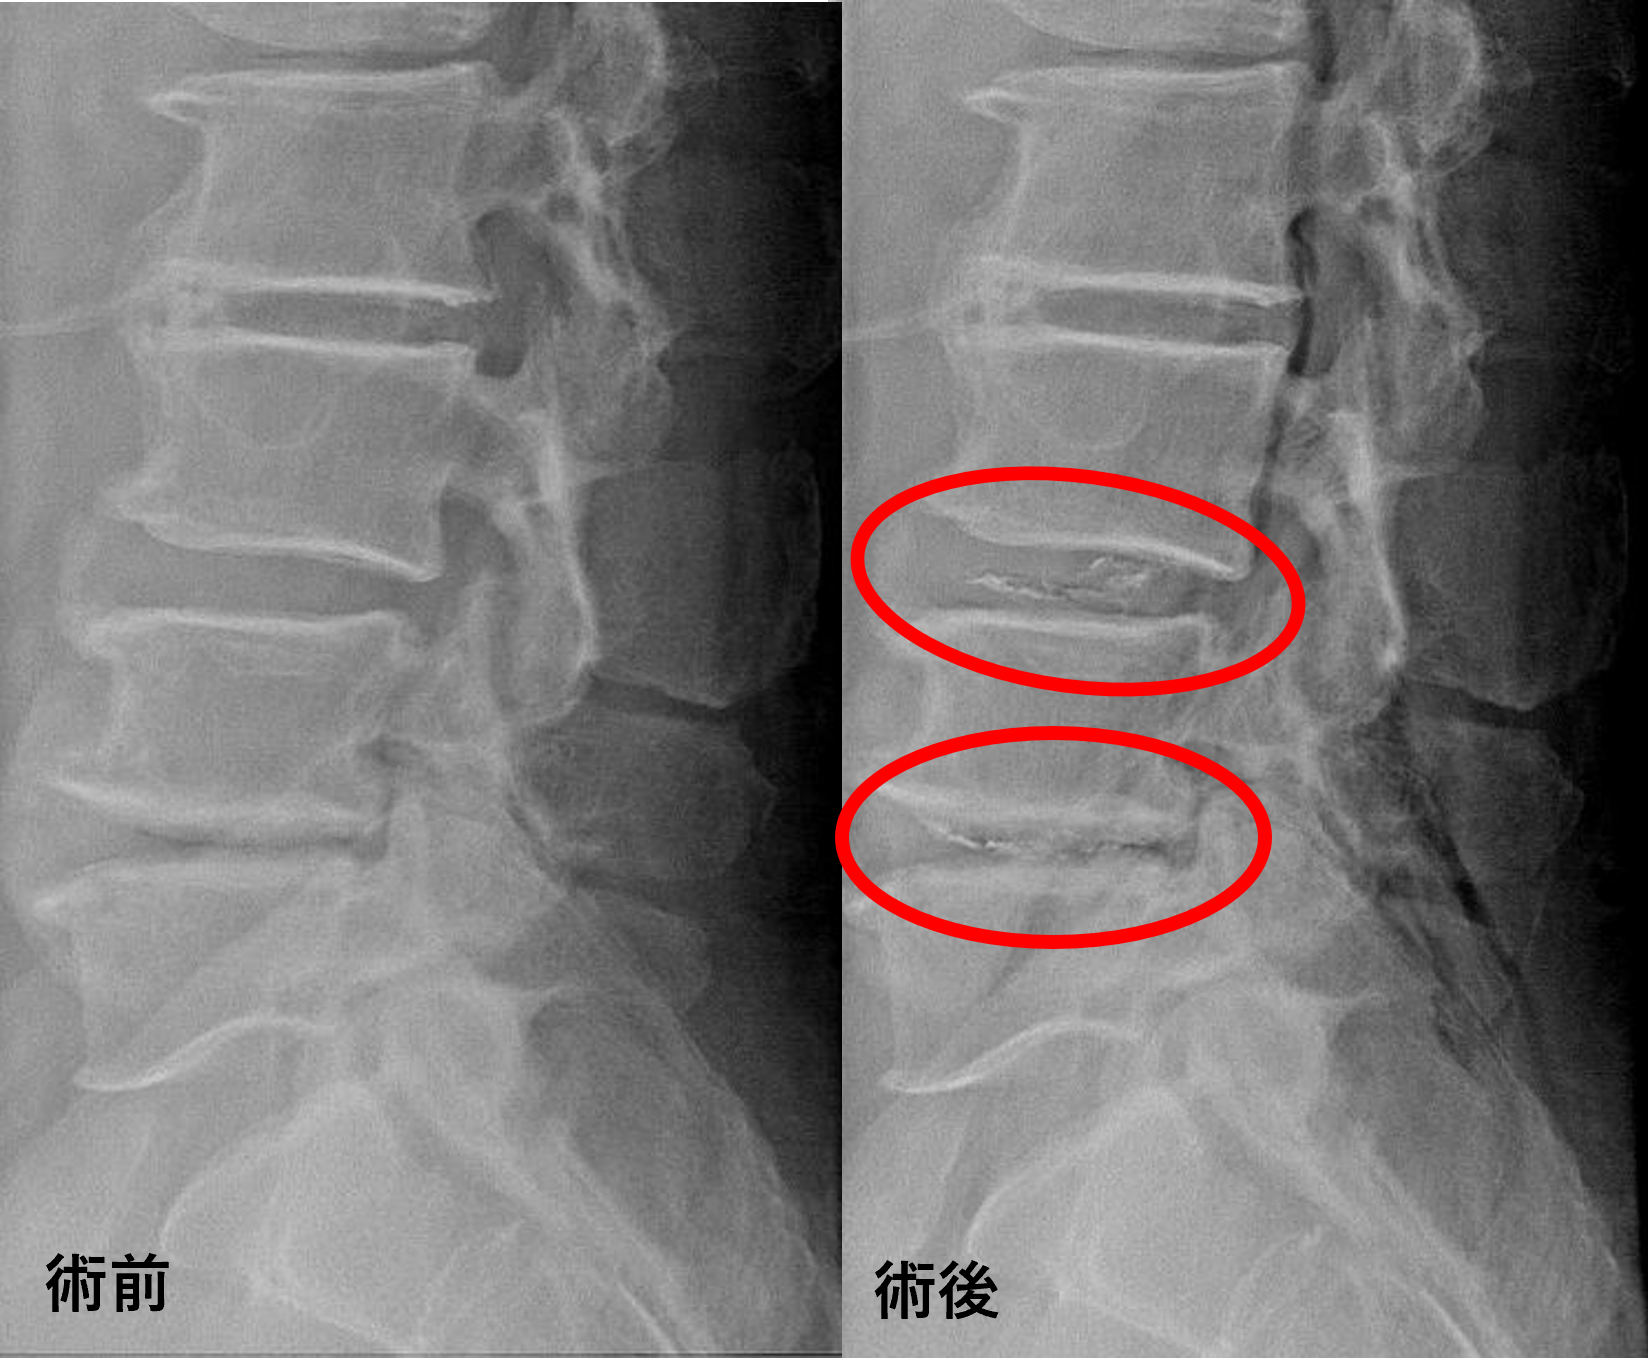

画像及び所見について

- L3/4、4/5 – 椎間板変性、膨隆、脊柱管狭窄

以上のことが画像上認められました。

L3/4、4/5の椎間板所見による脊柱管の圧排が、症状の原因の可能性が高い。

患者様と相談の元、L3/4、4/5にセルゲル法を施行